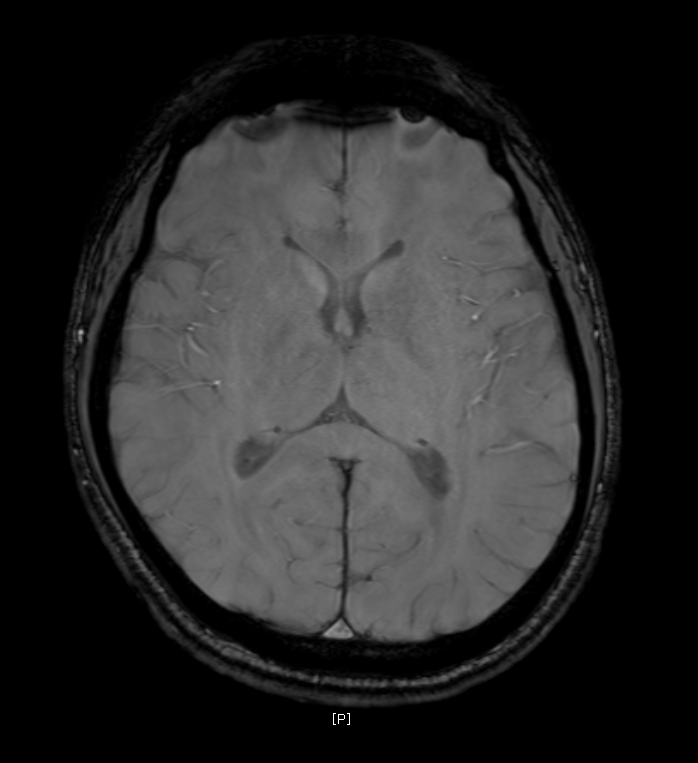

지난 금요일에 MRI를 촬영했는데요

혈관같기도 하고 하얀색 붕붕 뜨는 게 있어보이는데 (혈관같음)

한번 봐주실수 있나요? 그리고 전체적으로 괜찮은지도 봐주시면 감사하겠습니다.

특별하게 눈에 띄는 병변은 있어보이지 않습니다

말씀하신 것은 혈관의 가능성이 높겠습니다